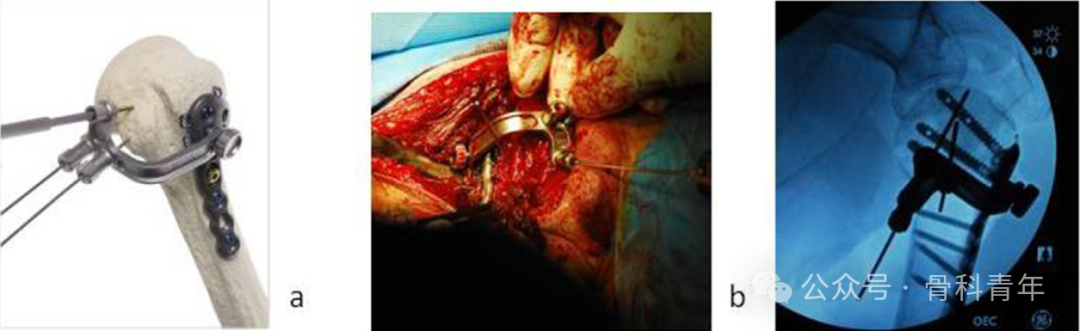

该手术的特点在于此特殊的低切迹钢板:钢板厚2.8mm,长73-220mm,3.5mm皮钉长10-45mm,5.28mm全螺纹钉长30-50mm,1.5mm交叉螺钉长20-35mm。钢板侧方具有便于缝合肩袖的侧夹,小螺钉可穿入近端5.28mm粗螺钉中。

常规三角肌胸大肌入路,复位骨折并临时固定后,将钢板放置于肱骨结节间沟后方,距离大结节顶点1-2cm,常规固定远近端螺钉。后通过外界导向架,经近端螺钉内置孔,置入1.5mm交叉螺钉(钉中钉)。